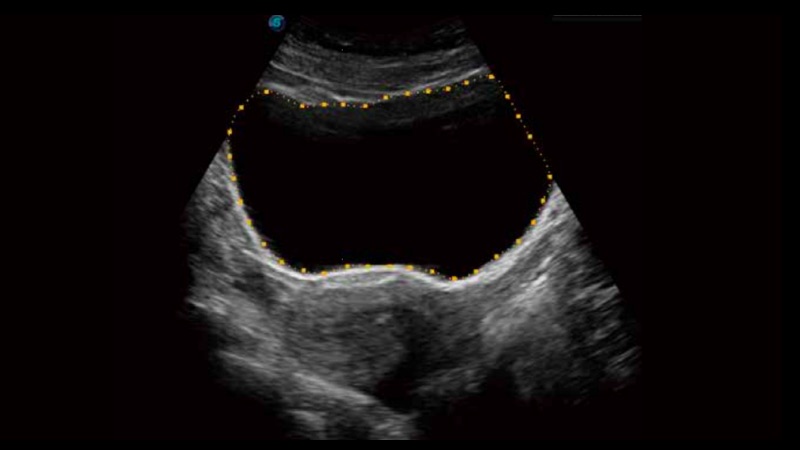

膀胱自動測量,一鍵式膀胱壁追蹤和容量測量可有效提供更精確的輪廓和結(jié)果,不受膀胱形狀和大小的影響。